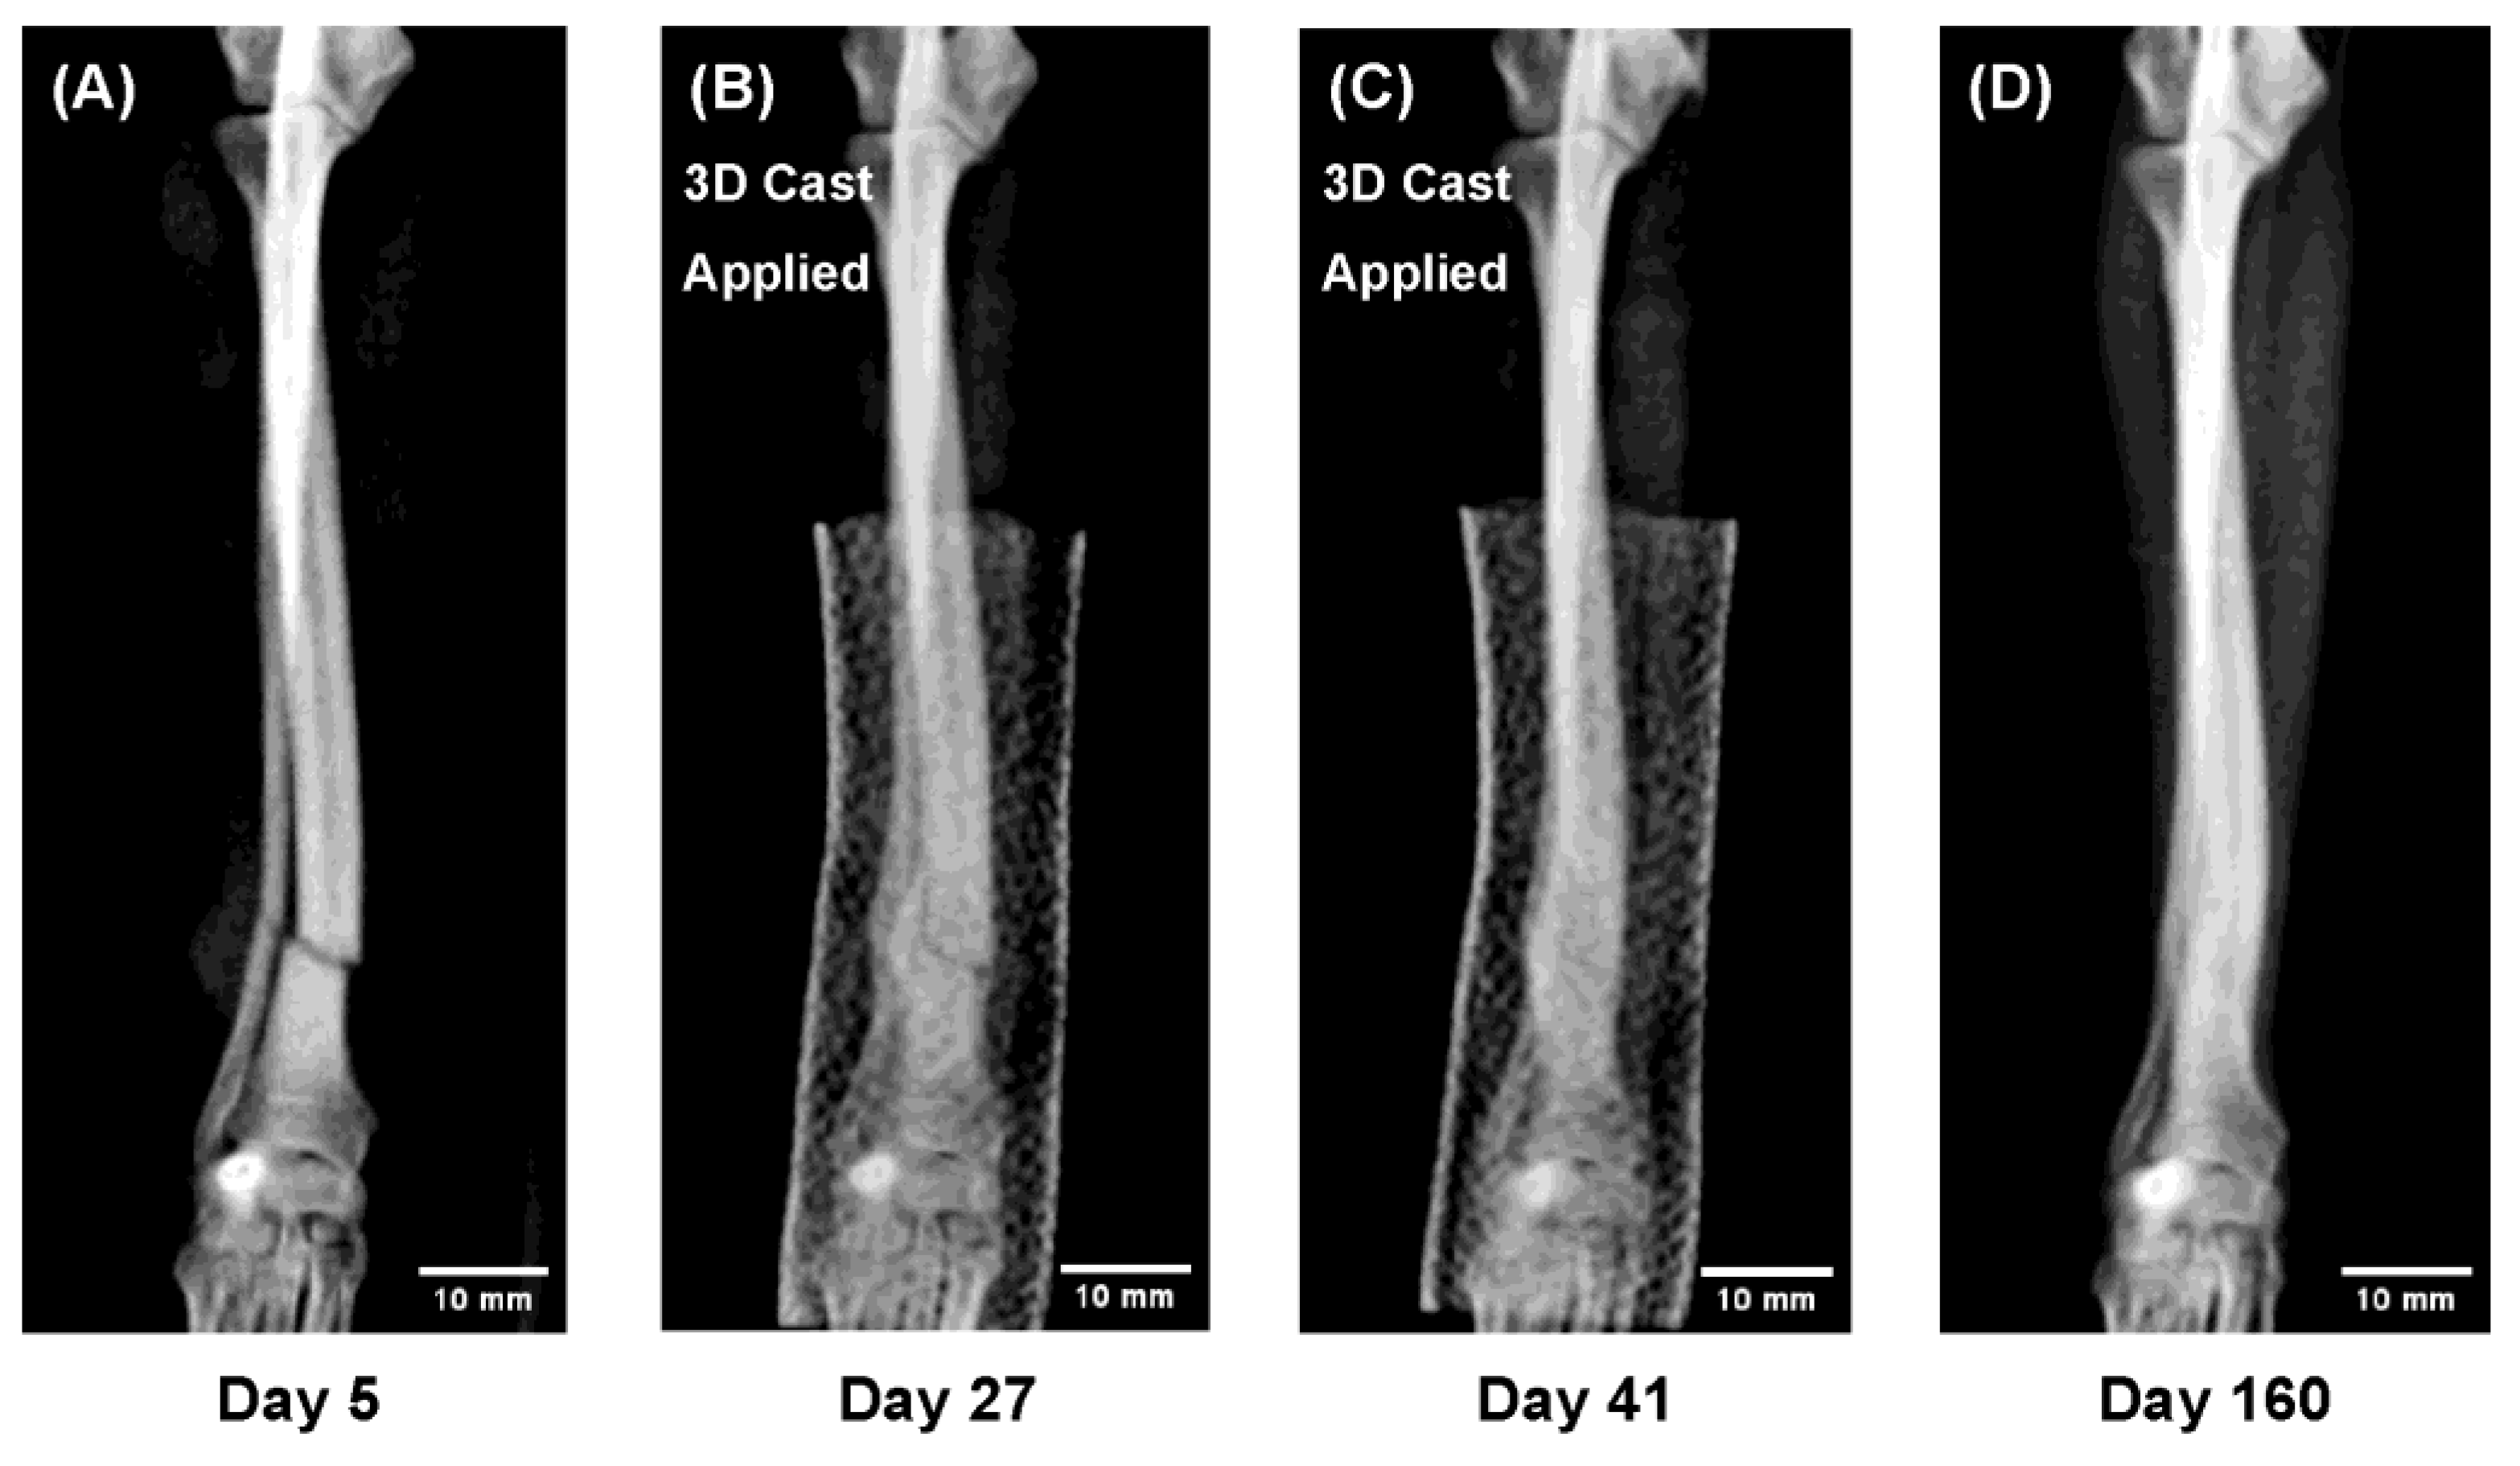

Figure 4.

Sequential radiographs showing radial–ulnar fracture healing under 3D cast treatment in a Pomeranian, 13 months old, 1.9 kg. Both the radius and ulna achieved union while the limb remained immobilized, allowing direct observation of indirect bone healing. The remodeling phase demonstrated trabecular reconstruction and restoration of the medullary cavity. (A) Day 5 after injury (3D cast applied on Day 9). (B) Day 27: callus formation and partial bridging. (C) Day 41: cast removal. (D) Day 160: complete remodeling and recovery of bone morphology.

Figure 4. In a 13 month-old Pomeranian with extremely slender bones, both the radius and ulna achieved complete union despite the low body weight. Continuous radiographi cmonitoring under immobilization revealed the full course of indirect bone healing, including bridging callus formation across both bones, trabecular reconstruction, and re-establishment of the medullary cavity during remodeling.